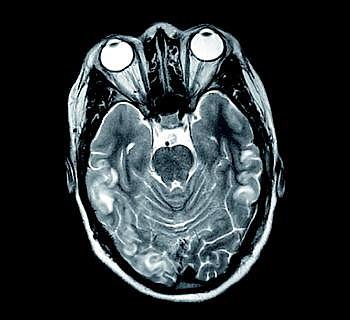

En 25-årig kvinde med præeklampsi fik generaliseret krampeanfald to dage efter fødsel (blodtryk 170/125 mmHg). Computertomografi (CT) af cerebrum viste bilaterale hypodensiteter overvejende occipitalt. Magnetisk resonans (MR)-skanning viste asymmetriske hyperintense signalforandringer på en T2-vægtet sekvens (billedet) kortikalt og subkortikalt i temporal- og occipitallapperne samt basalganglierne. På en diffusionsvægtet sekvens sås nedsat diffusion, som udtryk for intracellulært cytotoksisk ødem. Forandringerne på CT og MR-skanning var forenelige med posterior reversibel encefalopatisyndrom (PRES). Ved kontrol efter seks uger var patienten normotensiv og neurologisk helt intakt.

PRES ses ved eklampsi, nyresygdomme, transplantationer og autoimmune sygdomme [1] udløst af vasogent hjerneødem (75%) eller neurotoksicitet (25%) [2]. På MR-skanninger ses hyperintense læsioner hyppigst i områder, der er forsynet af a. cerebri posteriores, men også i vandskelsområderne og sjældnere i basalganglierne. Patienter med eklampsi har sværere forandringer og hyppigere involvering af basalganglier end andre patienter med PRES [3]. Normalt er der fuld klinisk og radiologisk remission, dog kan forandringer på den diffusionsvægtede sekvens være indikator for en blivende læsion.